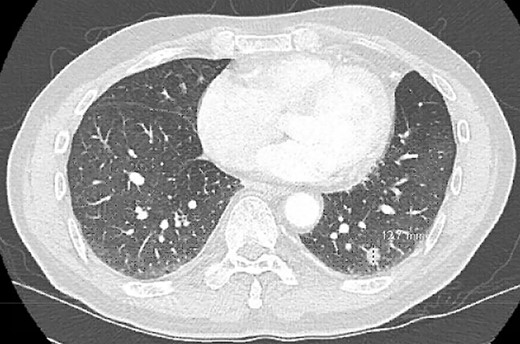

Postoperatively, the patient developed persistent expiratory air leak and thus underwent left VATS mechanical and chemical pleurodesis with Doxycycline on POD 4. Air leaks observed at previous staple lines were reinforced with additional staple loads, Floseal and Progel. In addition, an apical pleural tent was performed in the left upper lobe. He continued to have an expiratory air leak. Imaging on POD 13 demonstrated a BPF communicating with the pleural space (Fig. 2). Bedside pleurodesis with Doxycycline was performed through the thoracostomy tube.

POD13 CT scan demonstrating a BPF between the fifth and sixth ribs communicating with a pneumothorax and subcutaneous emphysema.